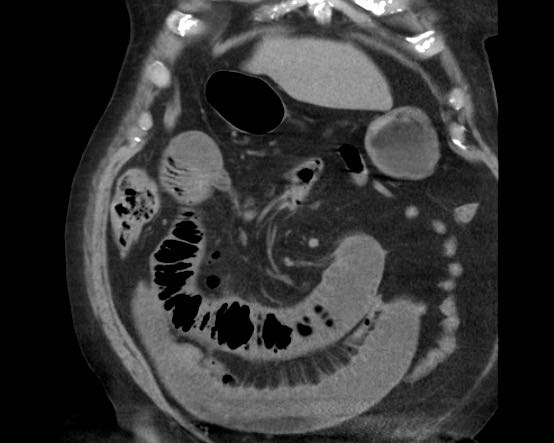

Đây là hình ảnh điển hình của tắc ruột do sỏi mật.

Lưu ý mức độ khó khăn khi phát hiện viên sỏi không vôi hóa.